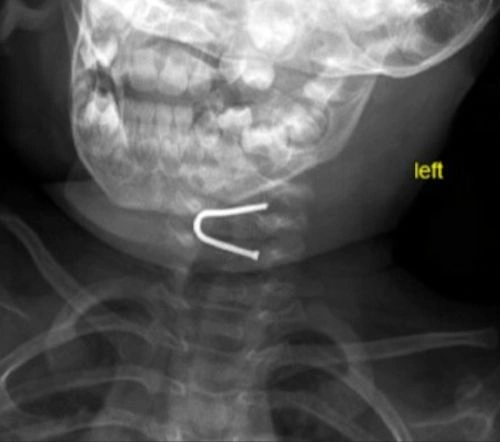

Körpənin mədəsindən mismar çıxarıldı